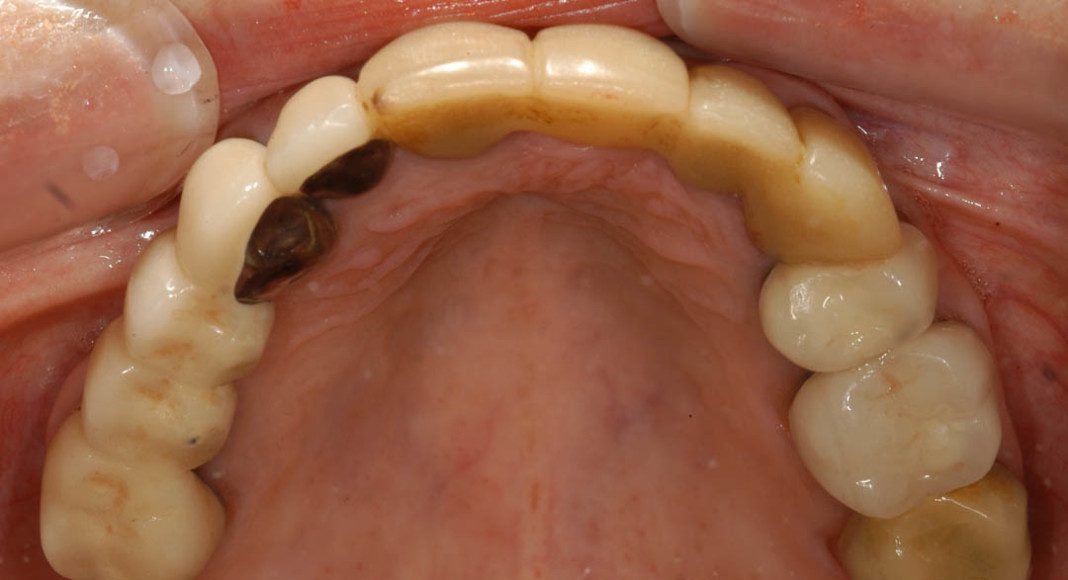

Final crowns, upper arch. (She didn’t need treatment on the upper left molar; it was still serving her well and didn’t have decay or problems. We figured, after 88 years, if it’s still strong and not posing any issues, leave it alone!)